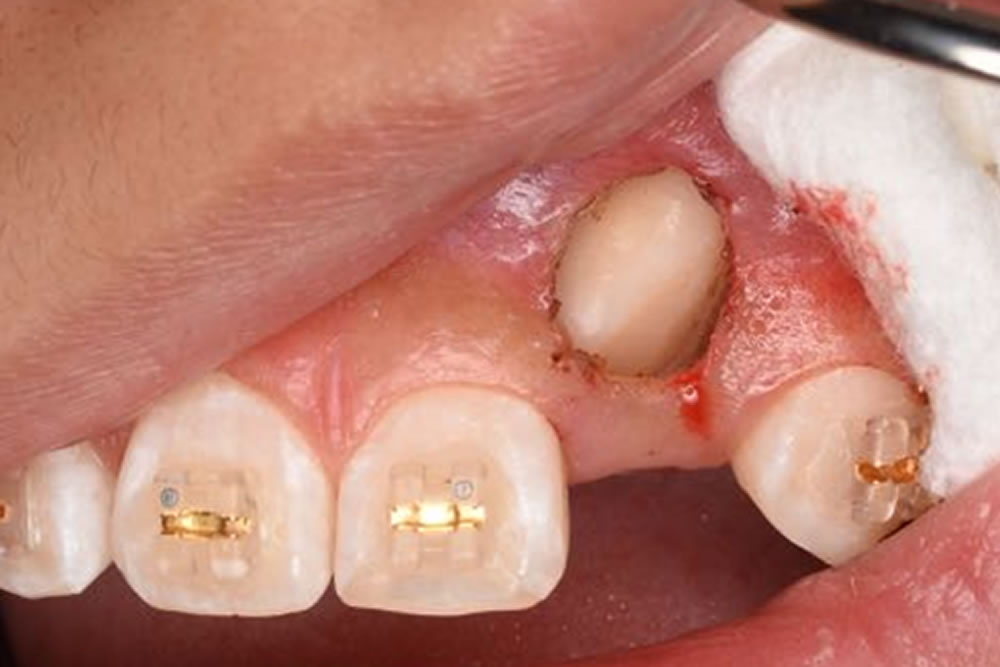

開窓牽引の実施

①CT画像にて外科的侵襲が最小限になるよう、開窓する部位を計画します。表面麻酔、浸潤麻酔をした後、電気メスにて歯肉を切除していきます。